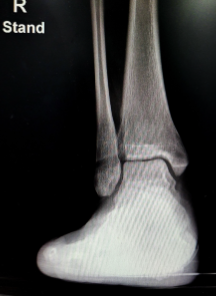

- 진단: 먼저 의사는 물리 검사, X-레이 및 MRI를 통해 인대 파열 정도를 확인합니다.

발목 인대파열 수술 후 회복 기간은 인대의 파열 정도, 수술 방법, 개인의 건강 상태 등 여러 가지 요인에 따라 달라집니다. 일반적으로 수술 후 6주에서 3개월 정도의 기간이 소요됩니다. 수술 후 첫 2주 동안은 부어 오른 발목을 고정하는 위축성 밴드를 착용하고, 안정을 위해 몇 일 동안은 보행을 금해야 합니다. 그 후에는 천천히 보행을 시작하며 근력 강화 운동과 유연성을 높이는 스트레칭을 해야 합니다. 수술 후 4주 이후에는 천천히 달리기나 스포츠 활동을 복귀할 수 있습니다. 하지만 수술 후 회복 기간은 개인별로 다르므로, 반드시 의사와 상담하고 전문적인 지도를 받아야 합니다.